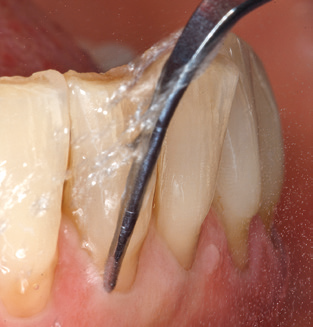

Of course, the use of instruments for mechanical removal of the biofilm is a central component of SPT and thus of primary significance. Consequently, the SPT workflow comprises both supragingival and subgingival cleaning. In our concept, a combination of hand instruments and machine cleaning has proven advantageous. A number of options are available for the mechanical procedures: sonic devices, ultrasonic devices and powder jet devices.

Although the fundamental principle of the ultrasonic devices remains, recent years have seen a whole host of further developments, resulting in an increase in efficiency, patient comfort and safety. These innovations are all present in the ultrasonic device (Tigon+, W&H Dentalwerk Bürmoos GmbH) currently employed by the authors, for example.

Good illumination of the working field facilitates the process considerably. The system used by the authors achieves this thanks to a 5x LED ring integrated in the handpiece. Naturally, a range of working tips for different indications is also offered. A straight, universally employable tip is the basic instrument required for machine cleaning of natural teeth (Fig. 5a and b). Curved tips, which allow access to exposed furcations, are also available for hard-to-reach areas in the posterior region (Fig. 6).

Fig. 4: Flexible probes with millimetre markings are recommended for the probing of dental implants (e.g. Colorvue Kit PCV11KIT6, Hu­Friedy). – Fig. 5a and b: A straight working tip (1P, W&H Dentalwerk Bürmoos GmbH) is a suitable instrument for use on all natural teeth. – Fig. 6: Curved working tips (3Pr/3Pl, W&H Dentalwerk Bürmoos GmbH) lend themselves to the processing of difficult-to-reach areas of the tooth and root surfaces (e.g. furcations). – Fig. 7: The tapered, hexagonal implant cleaning tip (1I, W&H Dentalwerk Bürmoos GmbH) permits atraumatic and efficient cleaning of the crown and abutment surfaces. – Fig. 8: Titanium and carbon curettes are suitable instruments for the manual cleaning of the implant surfaces.